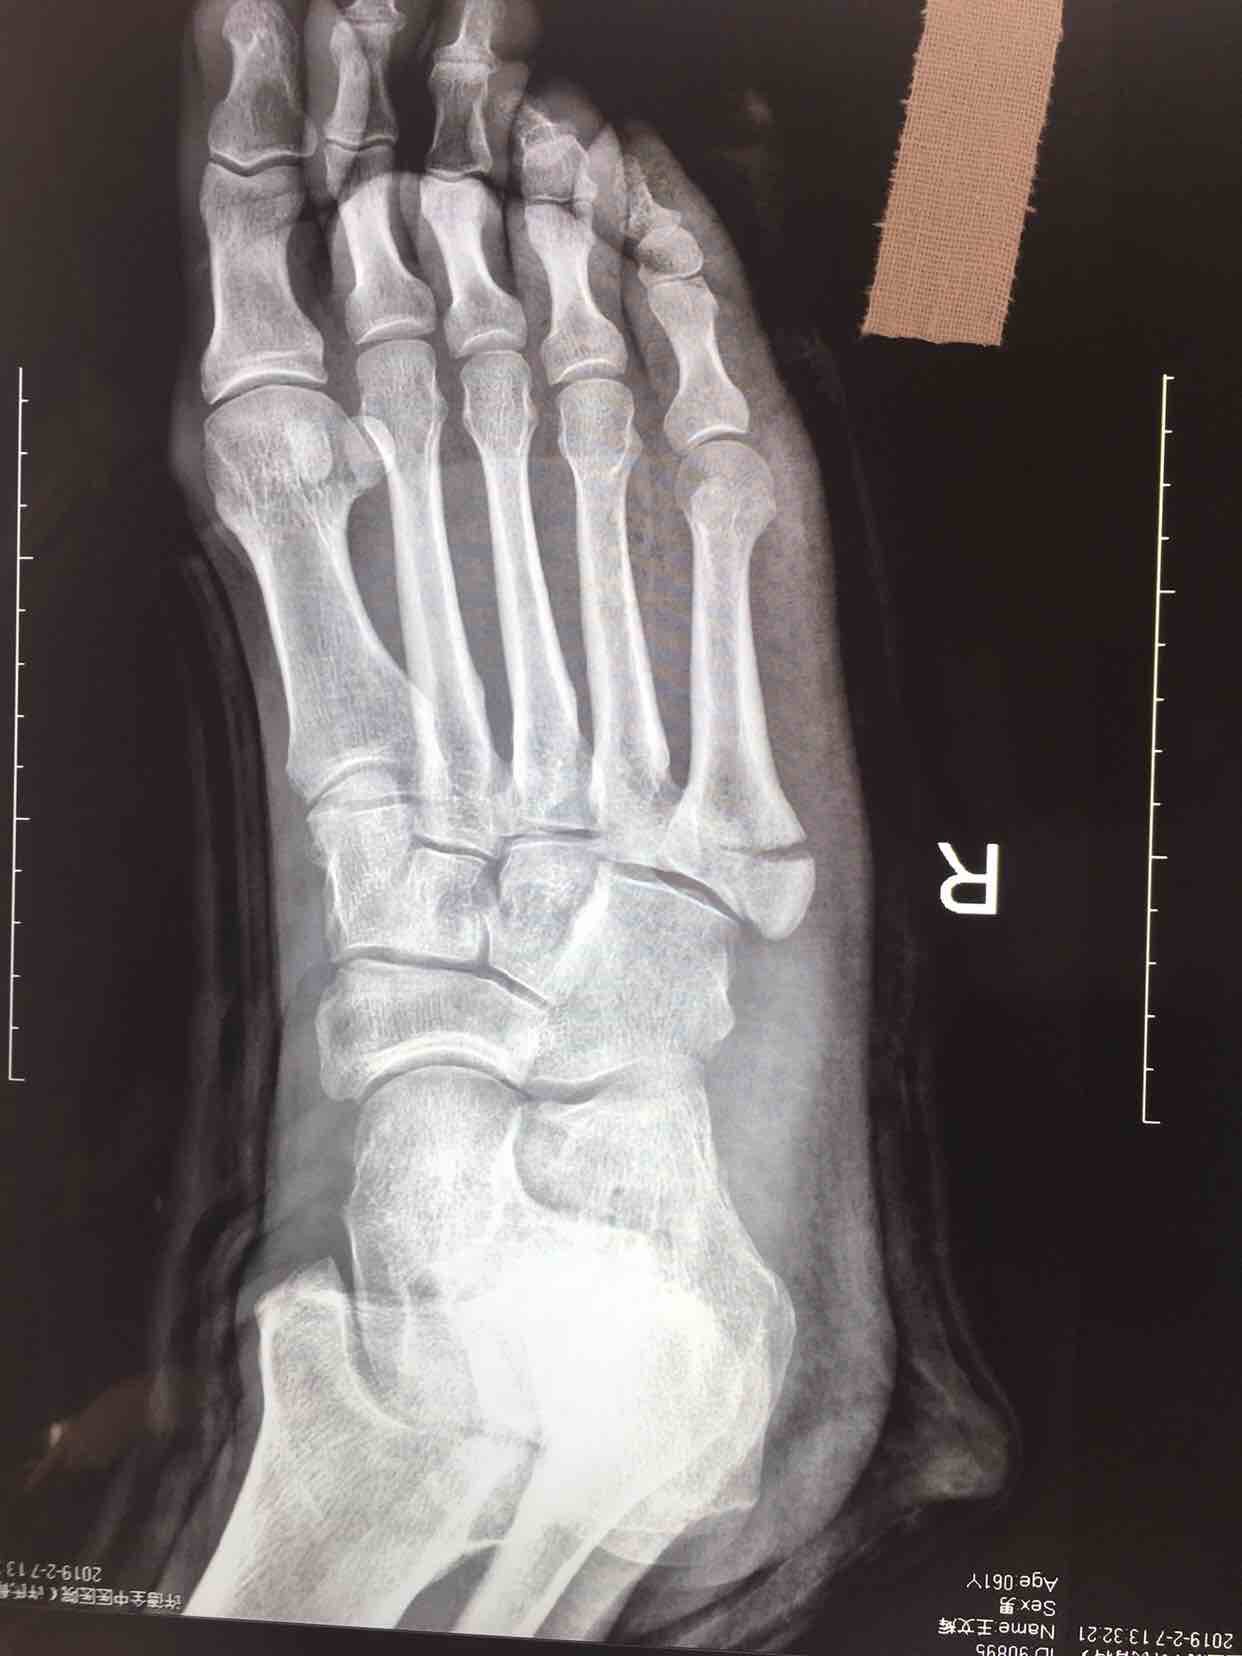

第五跖骨基底部骨折(切开复位内固定术)

摔伤后右足肿痛,活动受限16天入院。既往身体健康,无特殊不良嗜好。

心肺复未见异常,生命体征平稳。右足肿胀基本消退,局部皮色皮温基本正常,压痛及纵叩痛阳性,末梢血运感觉基本正常。

诊断第五跖骨基底部骨折(右)完善术前检查,在腰麻下行切复内固定术,术后抗炎,消肿等对症处理。